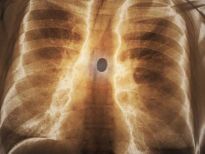

Bu röntgenler gerçek!

İki çatalı, bir tükenmez kalemi ve diş fırçasını yutmuş bir hasta.